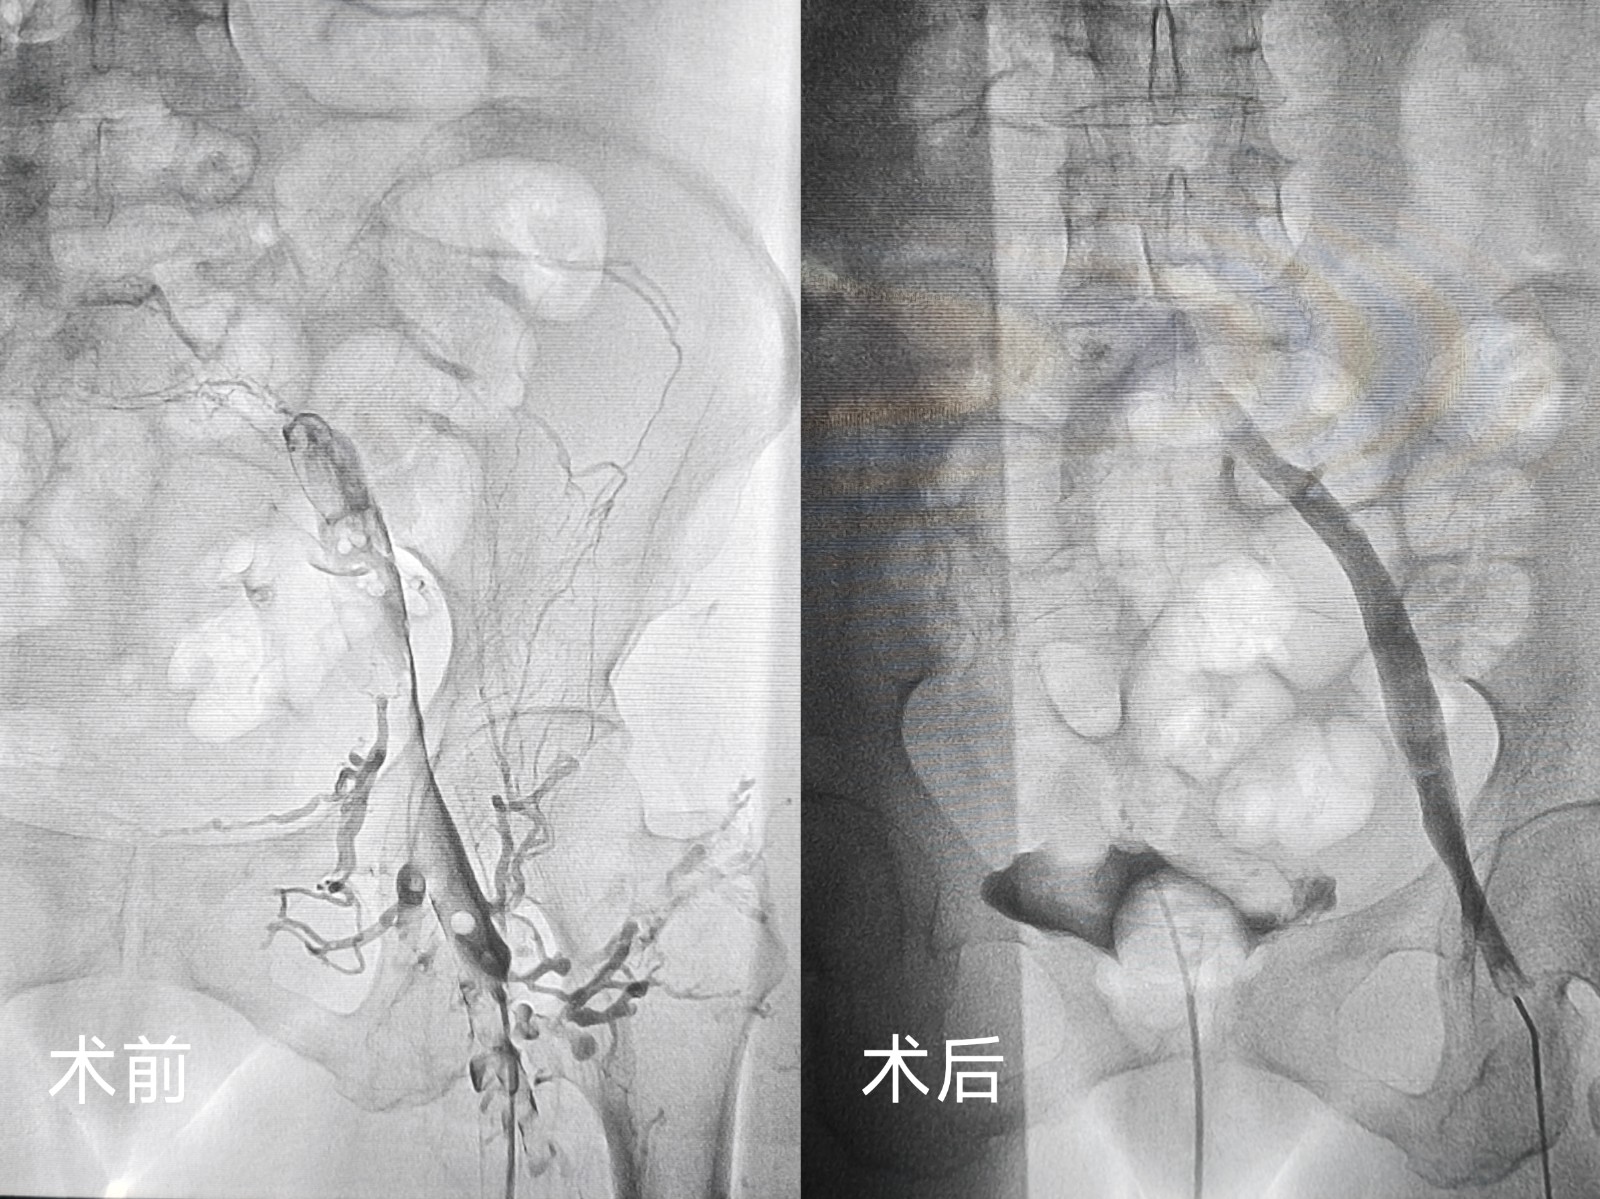

無獨(dú)有偶,一位左下肢突發(fā)腫脹伴劇烈疼痛的患者,在癥狀出現(xiàn)僅1天后便慕名前來求醫(yī)。患者病情進(jìn)展迅速,肢體腫脹明顯,疼痛難忍,嚴(yán)重影響正常行走??剖覉F(tuán)隊(duì)快速響應(yīng),經(jīng)詳細(xì)檢查后明確診斷為左下肢深靜脈血栓,隨即為患者安排緊急手術(shù)。術(shù)中,團(tuán)隊(duì)先為患者置入濾器預(yù)防肺栓塞,再運(yùn)用同款外周靜脈取栓支架系統(tǒng),精準(zhǔn)、高效地清除了下肢靜脈內(nèi)的血栓。

術(shù)后即刻,患者左下肢疼痛癥狀明顯緩解,腫脹程度顯著減輕,術(shù)后恢復(fù)期間,肢體功能逐步恢復(fù)正常,患者對治療效果贊不絕口。